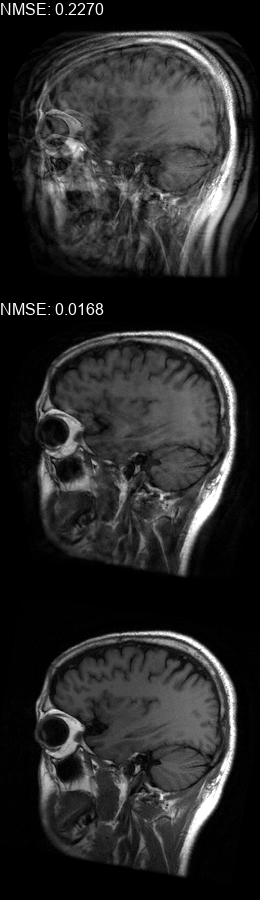

Results  Experimental results using the two presented datasets, for the fully-sampled and under-sampled k𝑘k-space scan orders, are shown in Table 1. The table presents the Normalized Mean Square Error (NMSE) obtained for each of the scan orders. For the Transaxial dataset, we only show the results for the challenging task where the DP contains only up to 707070 columns of k𝑘k-space data. All methods are able to reduce the NMSE of the corrupted scans, however the methods that incorporate the DC layer achieve a much better result. These results match our subjective visual impression of the motion-corrected images, as may be seen in Fig. 3 for simulated motion in a fully-sampled k𝑘k-space data, and Fig. 4 for an under-sampled k𝑘k-space data.

Figure 3: Motion corrected images from the Diverse dataset calculated using the 𝒮260subscript𝒮260\mathcal{FS}_{260} scan order presented in Fig. 1b. The bottom row shows the motion-free image. The top row shows the motion-corrupted images. The middle row shows the corrected images calculated using our method. (a) contains a motion at t1=87subscript𝑡187t_{1}=87, (b) contains two motions at t1=46subscript𝑡146t_{1}\!=\!46, t2=170subscript𝑡2170t_{2}\!=\!170, (c) contains three motions at t1=72subscript𝑡172t_{1}\!=\!72, t2=227subscript𝑡2227t_{2}\!=\!227, t3=248subscript𝑡3248t_{3}\!=\!248, (d) contains two motions at t1=112subscript𝑡1112t_{1}\!=\!112, t2=216subscript𝑡2216t_{2}\!=\!216, (e) contains a motion at t1=66subscript𝑡166t_{1}\!=\!66, (f) contains three motions at t1=65subscript𝑡165t_{1}=65, t2=135subscript𝑡2135t_{2}\!=\!135, t3=159subscript𝑡3159t_{3}\!=\!159.